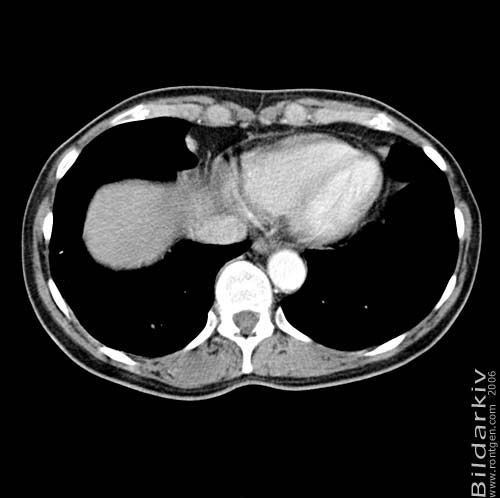

Thorax 46

Snitt över thorax med kontrast. Sk. mediastinum-fönstersättning.

CT Röntgen Helsingborgs lasarett

Mediastinum